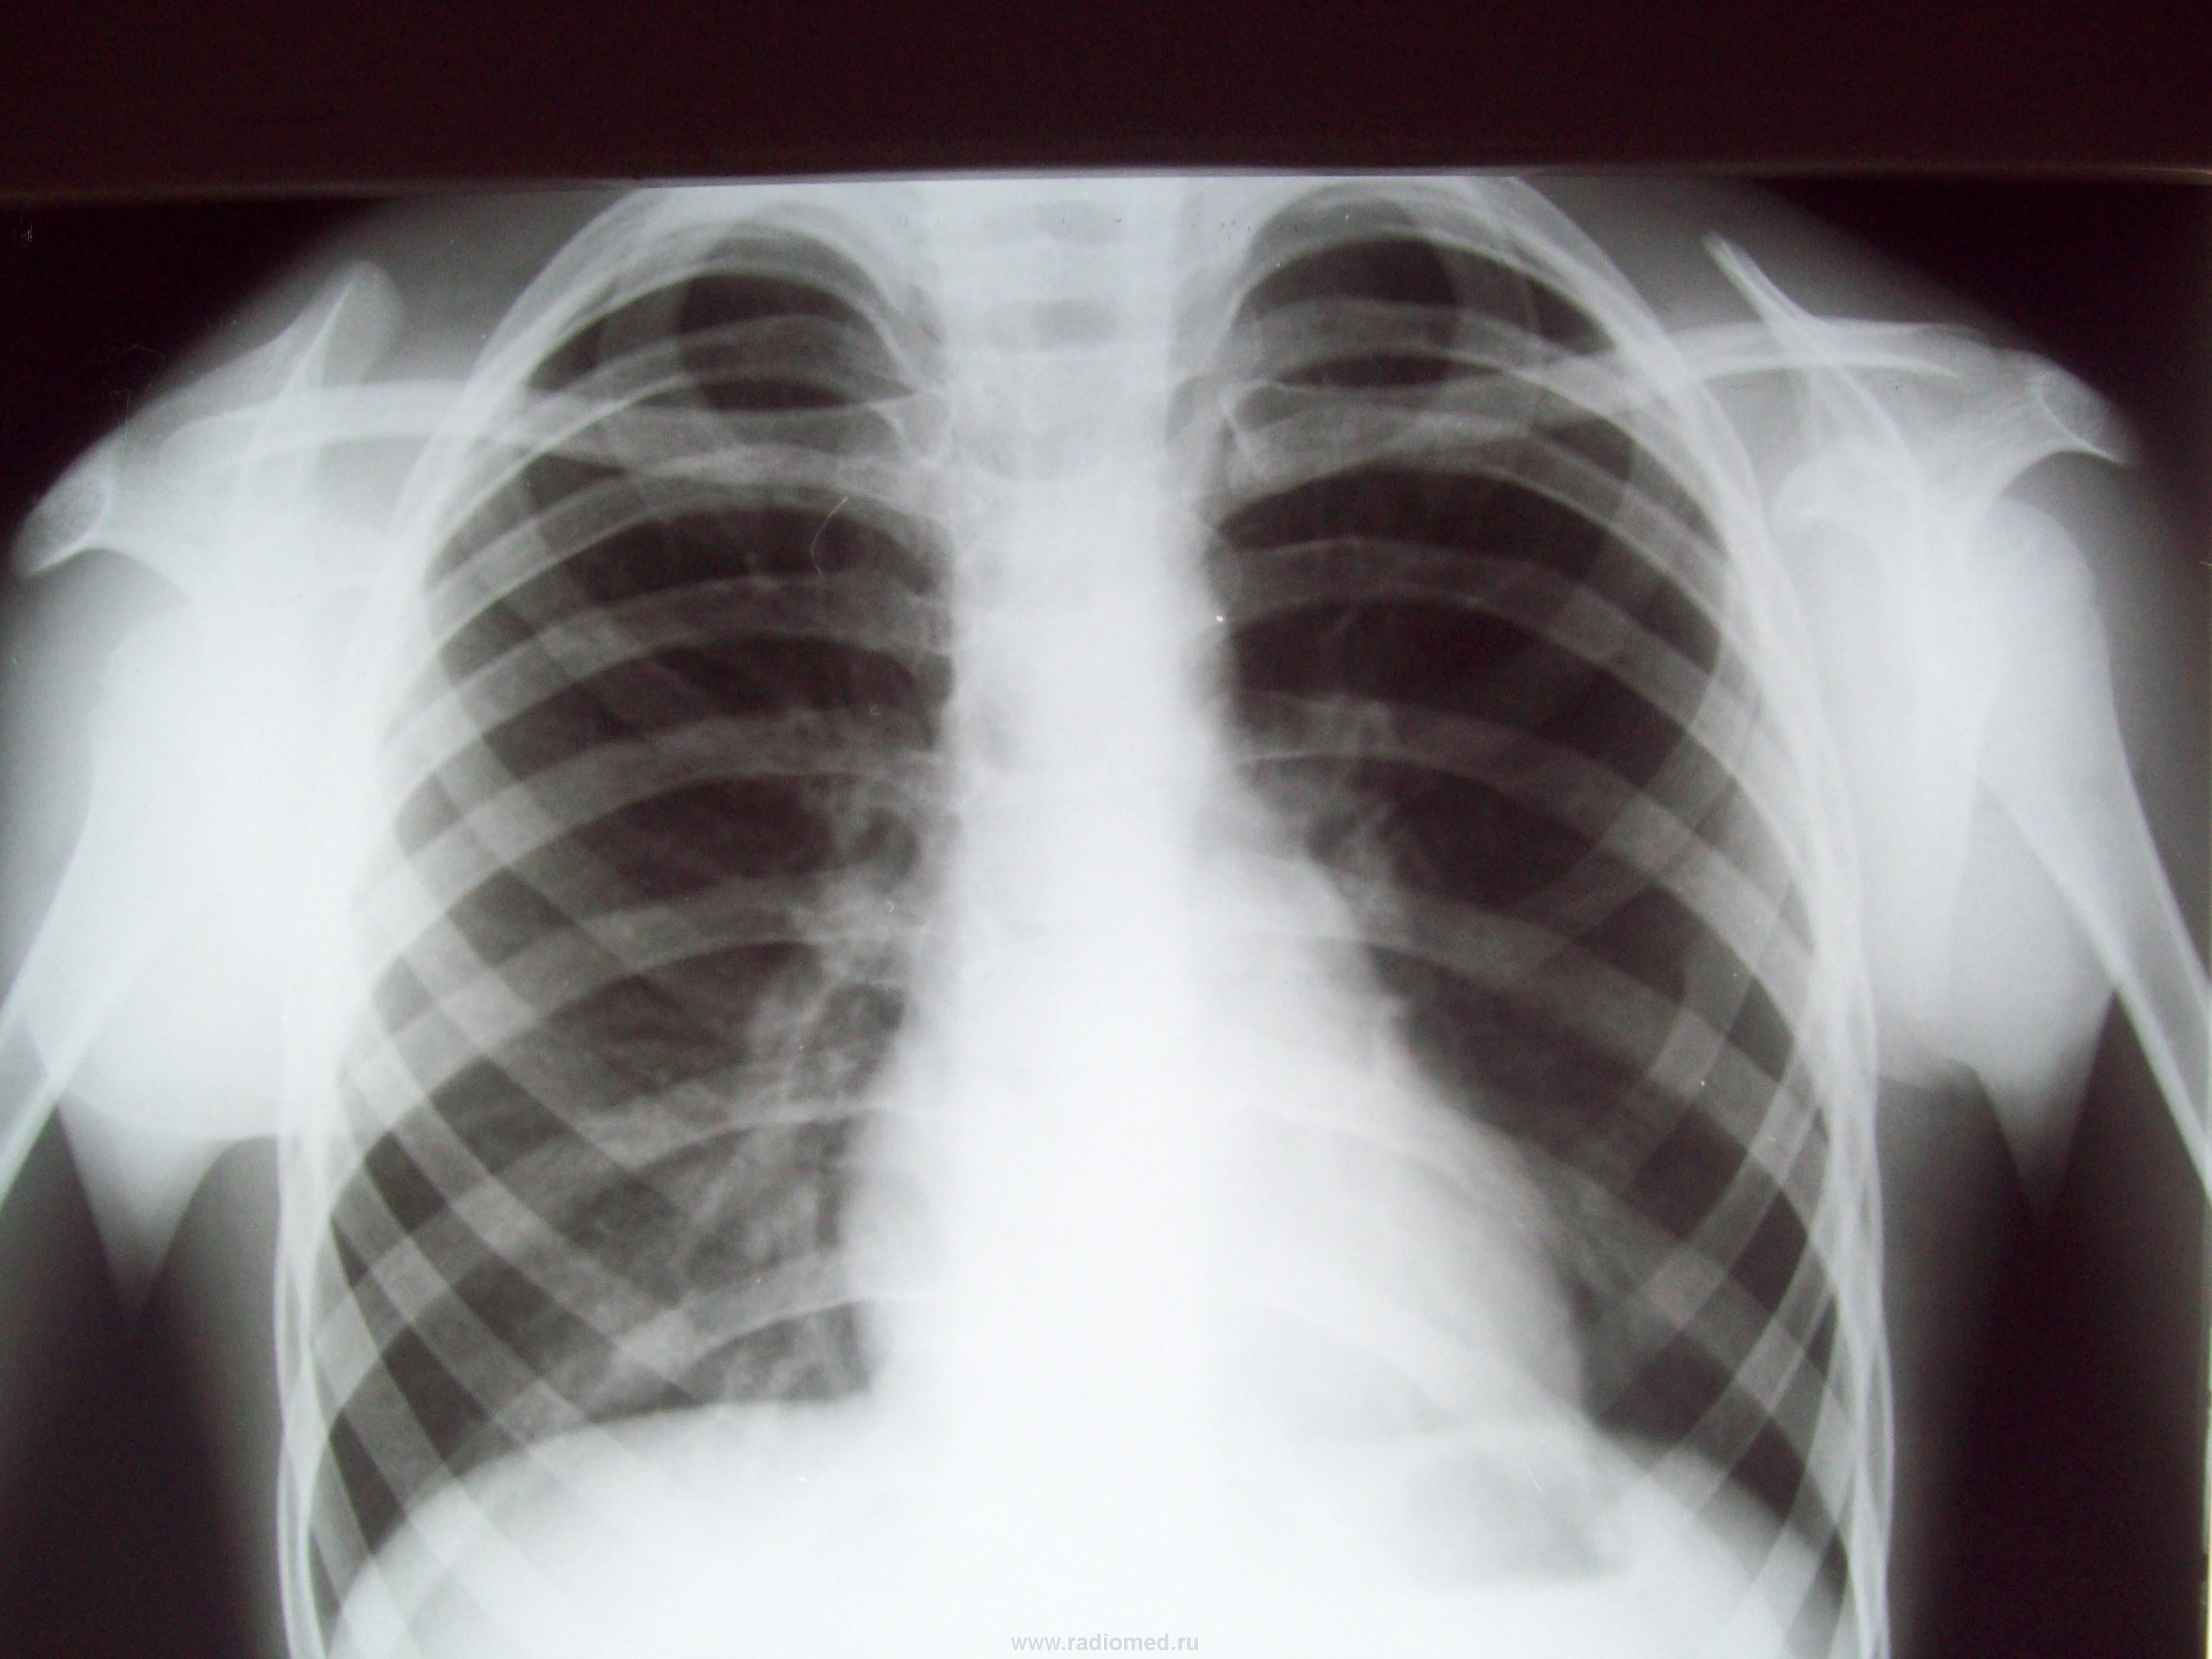

Пол пациента: Мужской пол Тип патологии: Воспалительное заболевание неинфекционной природы Область исследования: Грудная клетка и верхние дыхательные пути Методы исследования: Rg Гриппозное состояние; t , кашель , насморк. А что с ребром? Аномалия? ID:2505 Сб, 03/04/2010 - 01:30 #1 Петрович Не на сайте Был на сайте: 7 лет 2 месяцев назад Зарегистрирован: 22.03.2009 - 01:13 Публикации: 3908 На первый взгляд похоже. Но, поскольку, костная структура на изображении не видна, легко ошибиться. Если есть соответствующая клиника, стоит доснять ребро прицельно косо в рёберном режиме. Неоднозначно всё Сб, 03/04/2010 - 12:35 #2 stovbav Не на сайте Был на сайте: 2 года 2 месяцев назад Зарегистрирован: 20.12.2009 - 17:28 Публикации: 7066 Аномалия - вилка Люшка, но ассиметричная...вот всего и делов то... Болезни ног: виды, симптомы, причины, профилактика и лечение Сб, 03/04/2010 - 13:37 #3 Ola-la Не на сайте Был на сайте: 10 месяцев 1 неделя назад Зарегистрирован: 06.12.2008 - 09:33 Публикации: 1786 Нет, это не вилка Люшка. 3 и 4 ребра сближены по боковой поверхности, может, что-то типа синхондроза, но это точно вариант развития, такие встречала. https://www.instagram.com/pediatricradiology/ Сб, 03/04/2010 - 13:47 #4 stovbav Не на сайте Был на сайте: 2 года 2 месяцев назад Зарегистрирован: 20.12.2009 - 17:28 Публикации: 7066 Ola-la wrote: Нет, это не вилка Люшка. 3 и 4 ребра сближены по боковой поверхности, может, что-то типа синхондроза, но это точно вариант развития, такие встречала. Может и так, в принципе это не принципиально, да - расширение, да - сближение, но, как мне кажется, есть и небольшое раздвоение на переднем фрагментеПриложения: Болезни ног: виды, симптомы, причины, профилактика и лечение Сб, 03/04/2010 - 14:54 #5 Катенёв Валенти... Не на сайте Был на сайте: 7 лет 2 недели назад Зарегистрирован: 22.03.2008 - 22:15 Публикации: 54876 А может, и не аномалия, а может патология... Сб, 03/04/2010 - 15:03 #6 Катенёв Валенти... Не на сайте Был на сайте: 7 лет 2 недели назад Зарегистрирован: 22.03.2008 - 22:15 Публикации: 54876 "Ода" ребру! Приложения: Сб, 03/04/2010 - 15:09 #7 Катенёв Валенти... Не на сайте Был на сайте: 7 лет 2 недели назад Зарегистрирован: 22.03.2008 - 22:15 Публикации: 54876 Продолжение. Приложения:

На первый взгляд похоже. Но, поскольку, костная структура на изображении не видна, легко ошибиться. Если есть соответствующая клиника, стоит доснять ребро прицельно косо в рёберном режиме.

Неоднозначно всё

Аномалия - вилка Люшка, но ассиметричная...вот всего и делов то...

Нет, это не вилка Люшка. 3 и 4 ребра сближены по боковой поверхности, может, что-то типа синхондроза, но это точно вариант развития, такие встречала.

Может и так, в принципе это не принципиально, да - расширение, да - сближение, но, как мне кажется, есть и небольшое раздвоение на переднем фрагменте

А может, и не аномалия, а может патология...